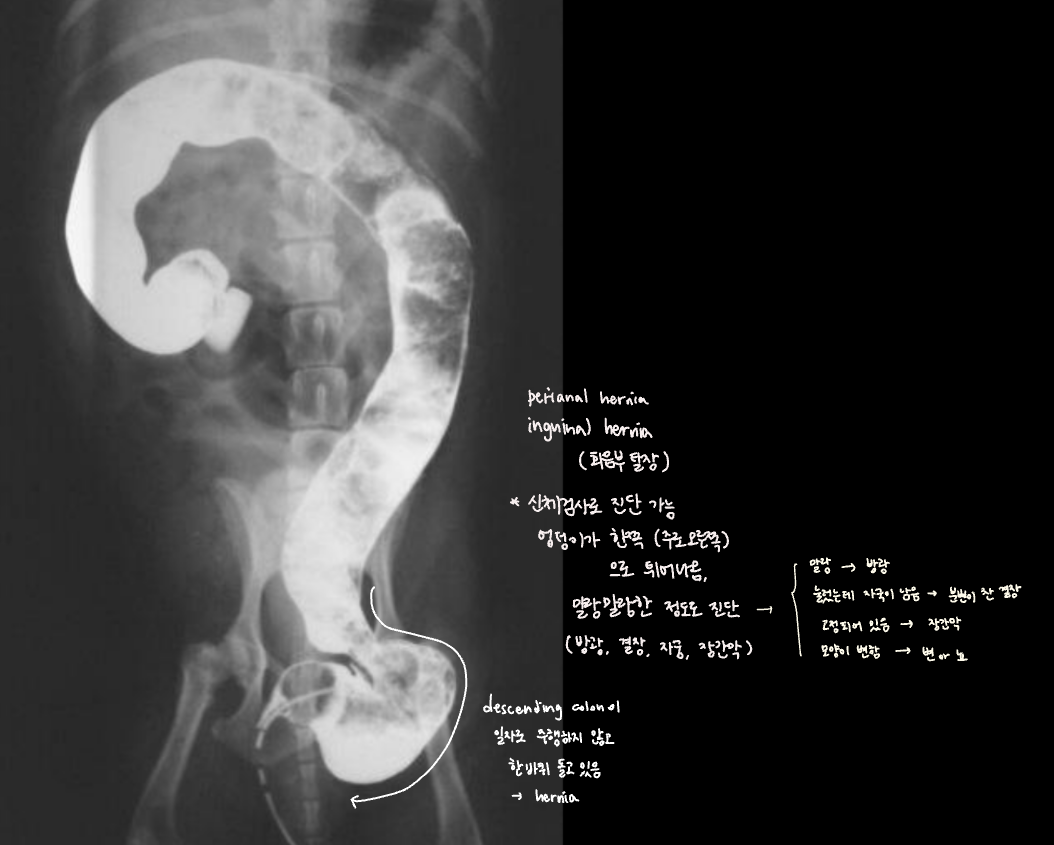

Inguinal/Perianal hernia